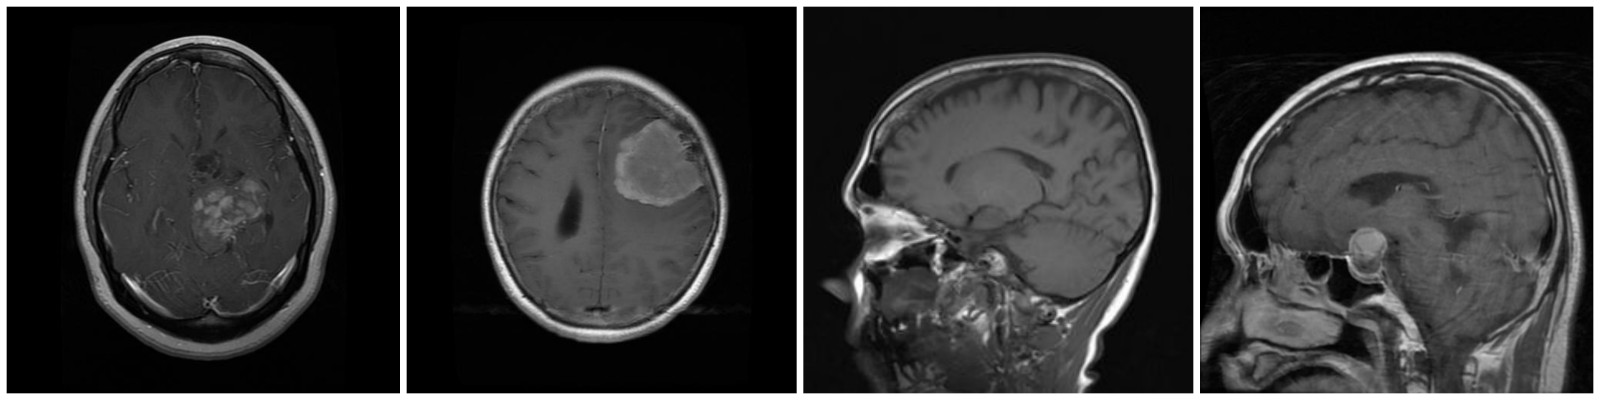

A brain tumor classification model based on ResNet-50. The impact of various data enhancements such as geometric transformations, Mixup, and SamplePairing are explored. The accuracy and stability of brain tumor MRI image classification is of great significance to the healthcare system, but the traditional model has the defects such as difficult to handle complex features and unstable classification. In this project, we propose a new brain tumor classification model based on residual neural network, using three different data enhancement algorithms, namely, geometric transformation, mixup, and SamplePairing, to process a dataset containing four different types of brain tumor images, and then evaluating the classification effect of the model, and we found that the accuracy of the proposed model is improved and more robust than the traditional model, among which the best result is achieved by using geometric transformation for data enhancement. Among them, the best results are achieved by using geometric transformation for data enhancement.

In today’s world, brain tumors are one of the most common diseases, therefore, research has been carried out for brain tumor image classification. However, the existing classification models still have some problems and defects in practical use due to the complex features and uneven distribution of brain tumor datasets. This project focuses on the problem of brain tumor MRI image classification, aiming to classify four types of images, namely, Glioma tumor, Meningioma tumor, No tumor, and Pituitary tumor, and optimize the model to make it have better classification effect. Firstly, ResNet-50 is chosen as the basic classification network for training, and the experimental results show that the classification correctness rate reaches 96.7%, with an F1-Score of 0.965. Based on this, we used three data enhancement methods, namely Mixup, Random Rotation, and SamplePairing to train the dataset, and obtained the performance of the models trained in these three cases on the The performance of the model in the test set is 97.3%, 98.0% and 97.8% respectively, and the F1-Score values are 0.974, 0.983 and 0.973 respectively, which shows the performance improvement compared with the model without data enhancement, and on the whole, random rotation brings the biggest improvement effect. This indicates that the data enhancement algorithm can be used to optimize the ResNet-50 network.